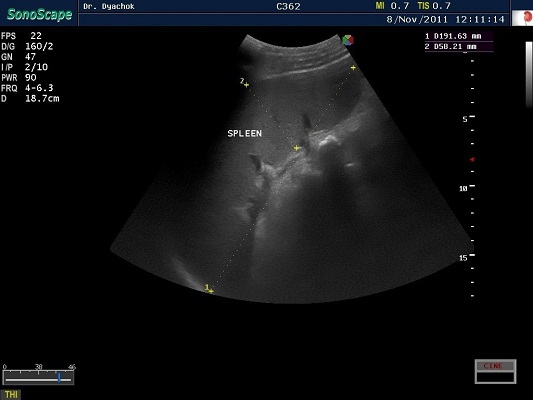

SonoScape S2N Vet – уникальная узи-система, выполненная в виде портативного ноутбука для легкой переноски. Отличается эта система цветным форматом визуализации, а также крайне чувствительными доплеровскими режимами, работающими на уровне премиальных аппаратов. При оптимальной цене – это очень хорошее и сбалансированное решение для ветеринарной клиники.

Диагональ монитора составляет 15,6 дюймов, что обеспечит комфортную работу для врачей и полный спектр визуализации для пациентов. Компактный вес не превышает 5 кг. (вместе с батареей), что оценят выездные бригады скорой помощи или ветеринары, выезжающие на дом.

Цифровая рабочая станция S2N Vet предполагает наличие жесткого диска для записи данных, составление и экспорт отчетов с возможностью добавления изображений, ведение базы данных пациентов.

Данный аппарат является незаменимым помощником в диагностической медицине. Ему нет конкурентов по оснащению, компактности и цене, а значит пора сделать правильный выбор для вашей клиники.